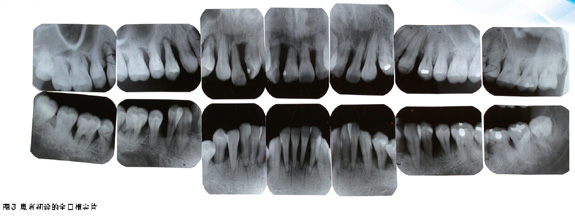

图1为患者初诊的口内相,图2为我们为患者进行检查的牙周记录表,图3为患者的全口根尖X线片,从中我们可以发现几个关键问题:①患者的口腔卫生较好,无明显龈上牙石,菌斑软垢也较少;②患者有广泛的深牙周袋和牙槽骨角形吸收,同时伴松动和溢脓情况;③患者全口牙列不齐,前牙深覆,21唇侧移位,11与12间、21与22间有2mm间隙,14、13与44对刃。